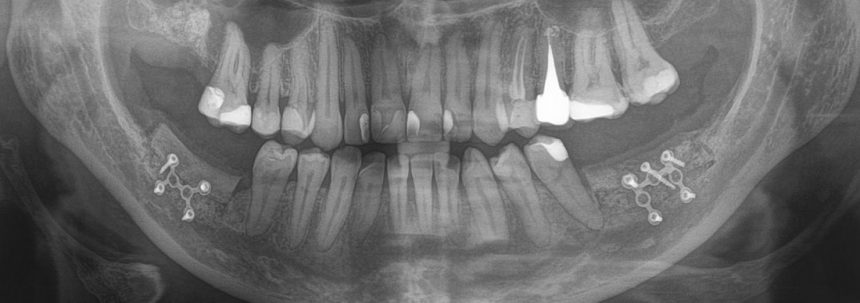

После операции:

— контрольный снимок (раньше делали ОПТГ, сейчас — строго КЛКТ)

Для этого мы сделали КЛКТ:

И КЛКТ показала нам, что с имплантатами и окружающей костью всё зашибись. Через 12 лет после операции, отсутствия наблюдения, пофигизма в замене временных коронок! Нужны ли тебе еще какие-нибудь доводы в пользу долгосрочной эффективности метода?

Серия контрольных снимков на этапах: